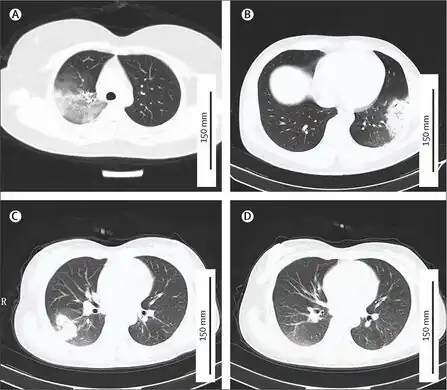

a-d)CTs of individual with Chlamydia psittaci infection -